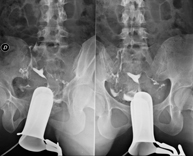

La urografia intravenosa (UIV) consisteix en l'obtenció d'imatges radiològiques seriades del ronyó, vies urinàries i bufeta. Aquest estudi requereix sempre l'ús d'un contrast iodat. - Cistografía (CUMS)

La cistouerotrografia miccional seriada consisteix en l'obtenció d'imatges radiològiques per valorar l'anatomia i la funció de la uretra i la bufeta amb l'administració de contrast iodat a través d'una sonda vesical. - Uretrocistografia (Uretro-Cums)

La uretrocistrografia retrògrada i miccional consisteix en l'obtenció d'imatges radiològiques per valorar l'anatomia i la funció de la bufeta i de la uretra. S'aplica material de contrast a través d'una petita sonda que es troba a la uretra i s'obtenen imatges durant l'ompliment i el buidatge de la bufeta. - Pielografia ascendent per catèter

Prova diagnòstica que consisteix en la visualització de l'urèter i de la pelvis renal mitjançant l'ús de raigs X en aquells pacients portadors d'un catèter mitjançant la injecció d'un contrast iodat a través del catèter.

- Pielografia per nefrostomia

Prova diagnòstica que consisteix en la visualització del tracte urinari mitjançant l'ús de raigs X en aquells pacients portadors d'un catèter de nefrostomia mitjançant la injecció d'un contrast iodat a través del catèter.

- Hipsterosalpingografia (HSG)

Prova diagnòstica que consisteix en la visualització i l'estudi de l'úter i les trompes de Falopi mitjançant l'ús de raigs X i un mitjà de contrast. La pacient haurà de realitzar un tractament antibiòtic profilàctic i es recomana la presa d'un sedant suau una hora abans de la prova. - Trans-Kher Cholangiography

- Cystography

Serial voiding cystourethrography involves radiological imaging to assess the anatomy and function of the urethra and bladder with the administration of iodinated contrast through a bladder catheter.